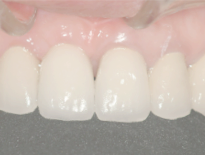

右の前歯が一本ありません。

最初の仮歯の状態です。